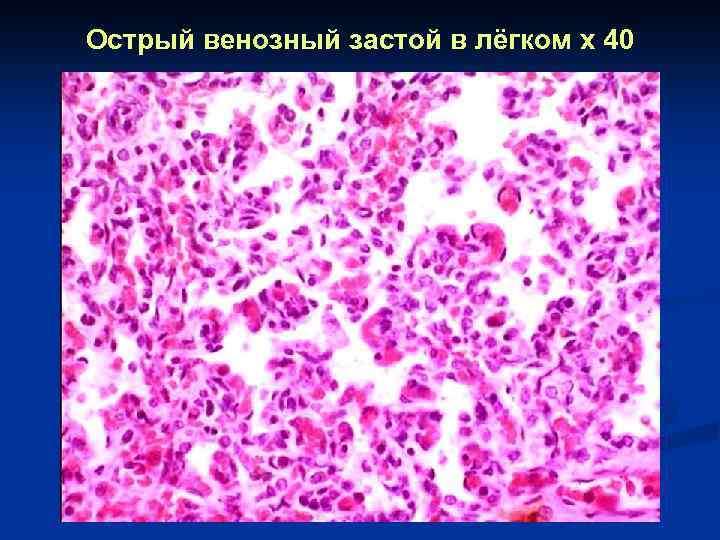

Острый венозный застой в лёгком x 40

Острый венозный застой в лёгком x 40

Острый венозный застой в лёгком x 40